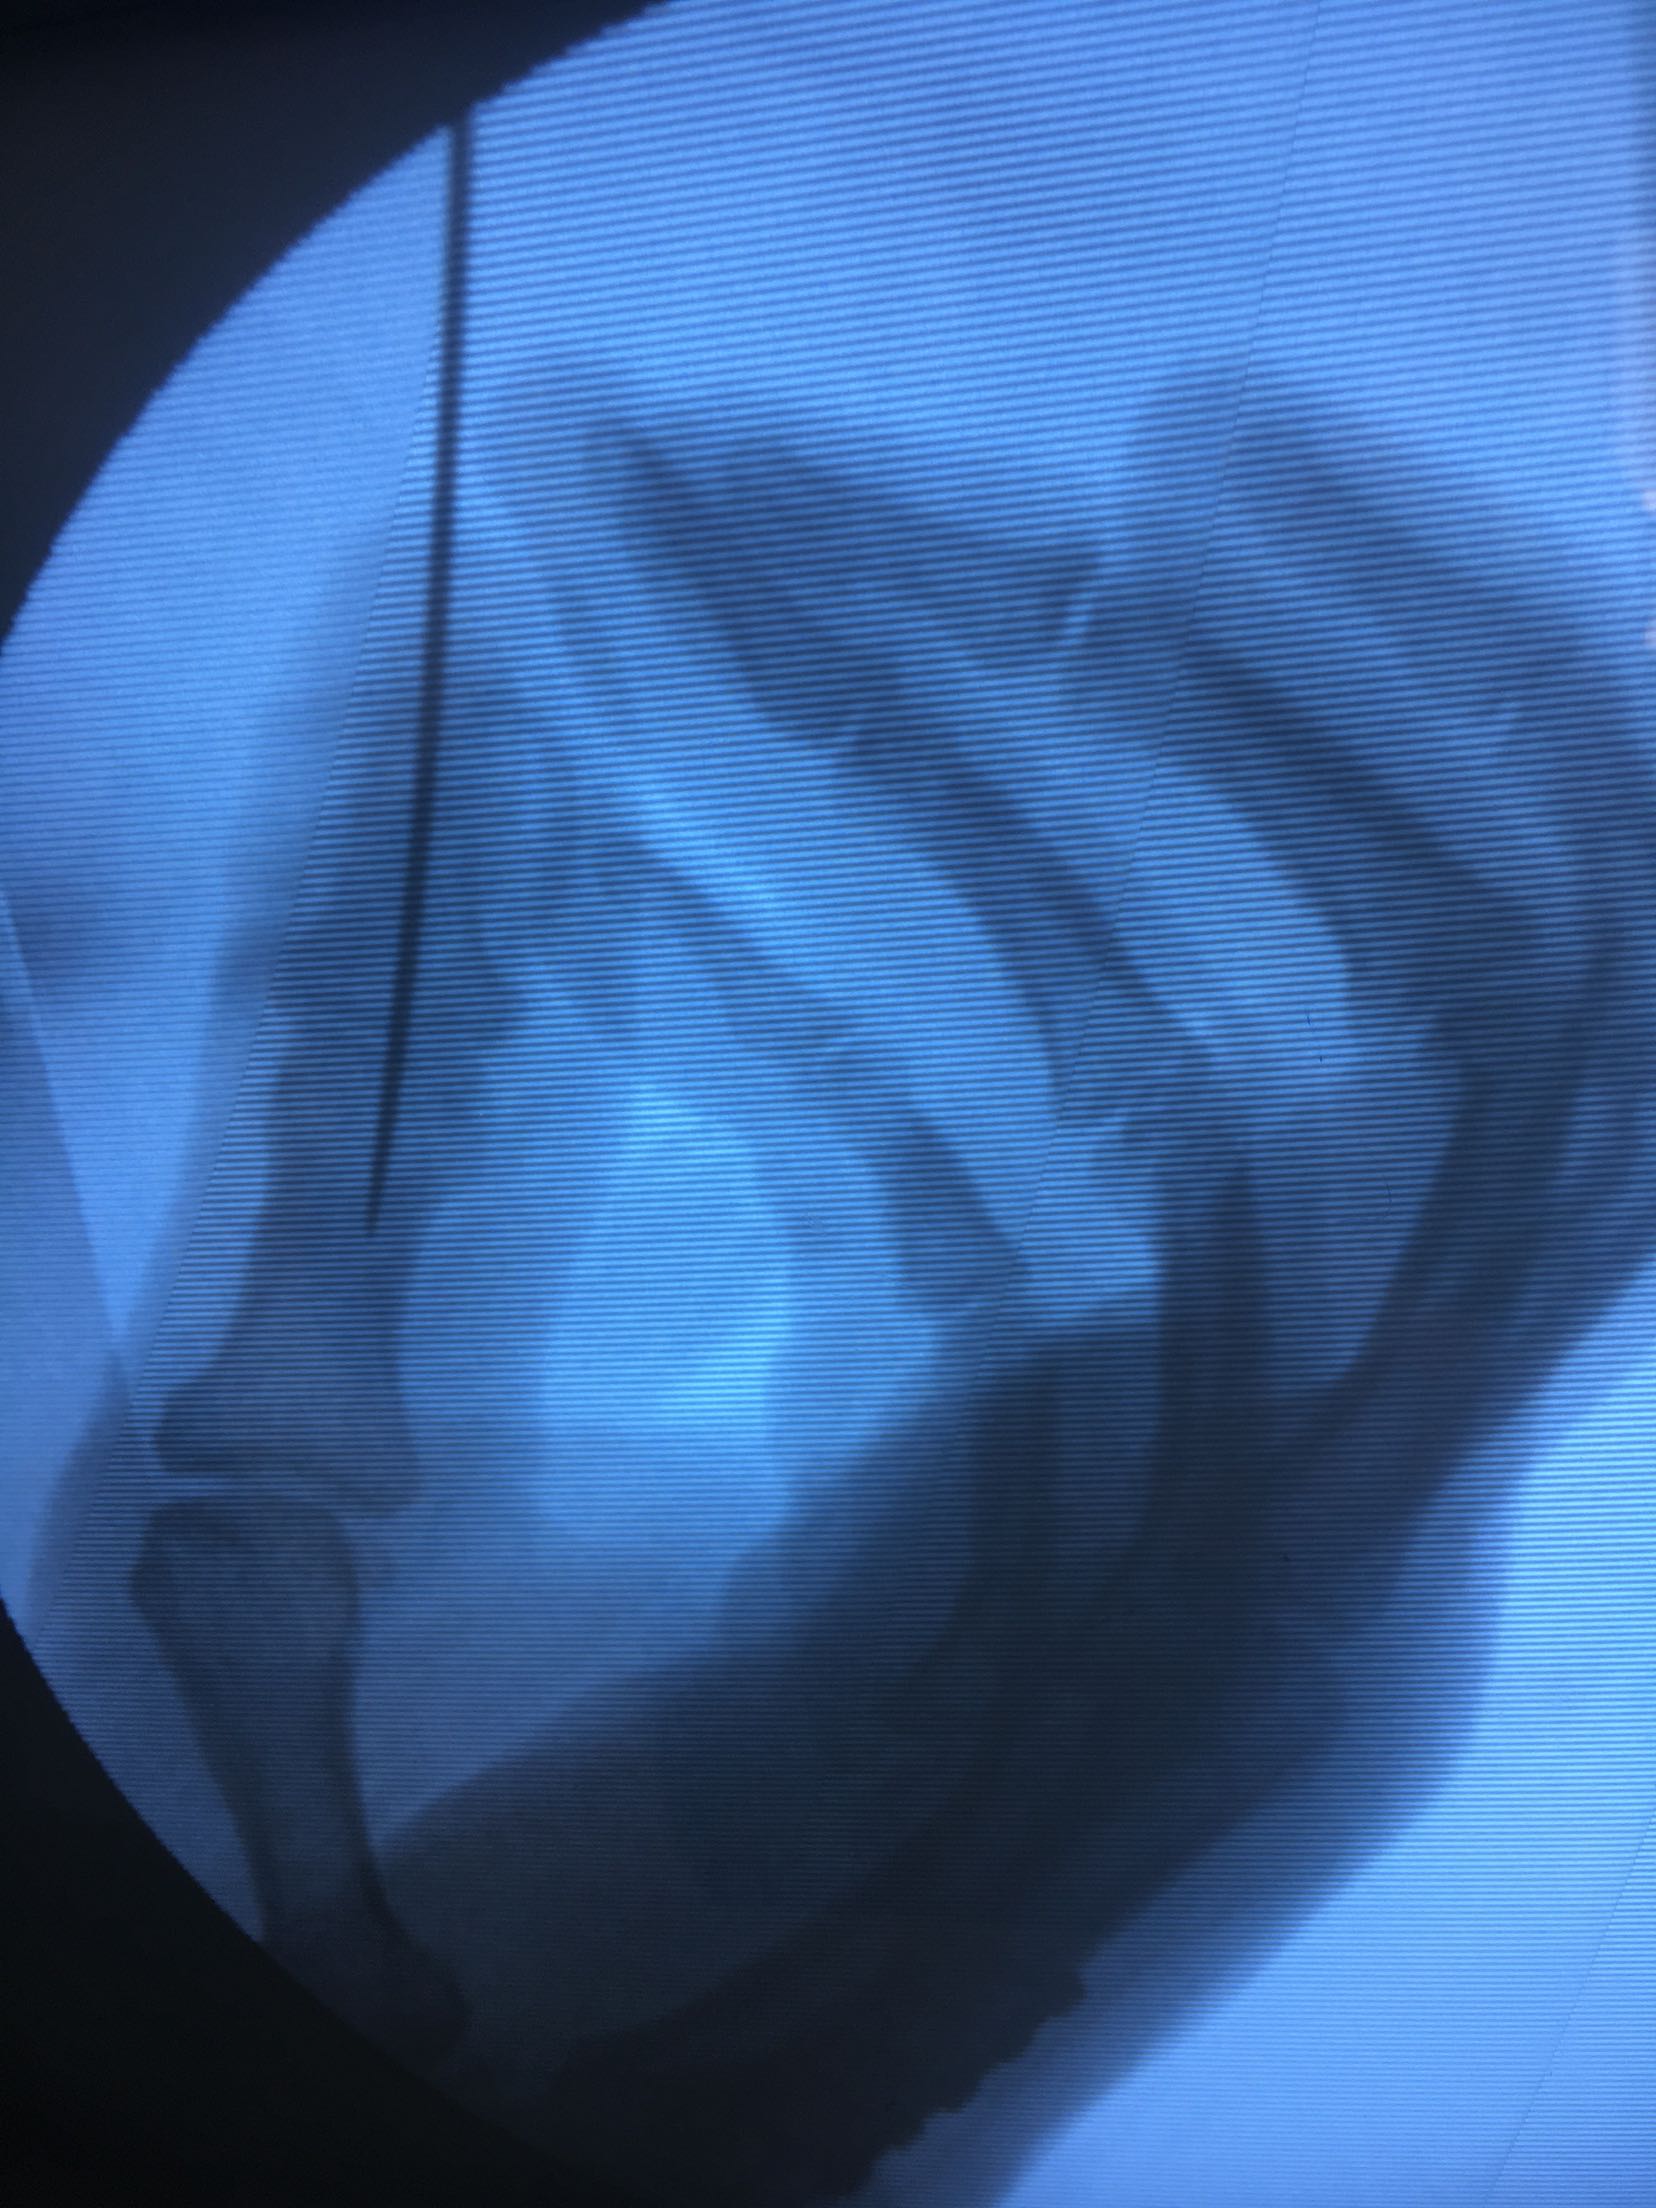

积极术前准备,在臂丛麻醉下行锤状指伸指功能重建术,掌骨骨折切复内固定术,术后抗炎,消肿对症处理。<img src=https://pub-voice-video.medlinker.com/9129333F-3928-47F0-B39A-978756FECFAD><img src=https://pub-voice-video.medlinker.com/945D4FD6-D0B7-41EF-ABB0-C2940D6C2E54><img src=https://pub-voice-video.medlinker.com/2F847276-23A8-4CAF-BF99-1828976F7BAD><img src=https://pub-voice-video.medlinker.com/2996EABA-9281-4CC0-8612-66A515AC6472><img src=https://pub-voice-video.medlinker.com/D3EFB6D4-D26D-4778-B65E-2D52DD5235E7><img src=https://pub-voice-video.medlinker.com/9197F543-FC48-48BB-BA43-DDBEEE8749C0><img src=https://pub-voice-video.medlinker.com/109E9BC2-A473-4E71-B880-027E2D1DF300>